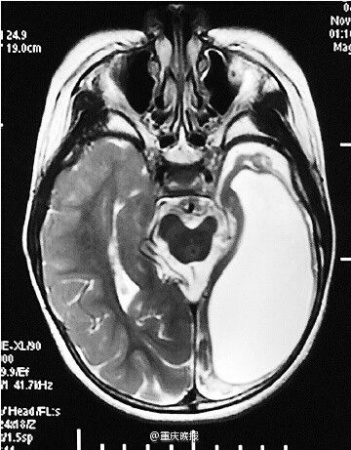

贵州省桐梓市的8岁男孩松松(化名)只有半个大脑,说话走路毫无障碍。8年前,他刚出生不久,大脑不慎受伤,癫痫频发。3年前,他来到新桥医院切除左半脑。近日,他回到医院进行复查,已经完全康复,可以正常生活。

2012年底,父母带着松松前往第三军医大学新桥医院全军癫痫诊治中心就诊,发现他的左侧大脑组织几乎完全软化,左侧脑室已经没有正常的脑组织。医生为松松进行头部脑电图检查时还发现,左侧大脑位置有异常的脑电波。

新桥医院外科主任杨辉教授介绍,专家们判断松松左侧大脑功能几乎完全丧失,而且左半球大脑发出的异常脑电波还干扰了右侧大脑功能,影响说话和行动。医生随即将其左侧的大脑半球完整切除。